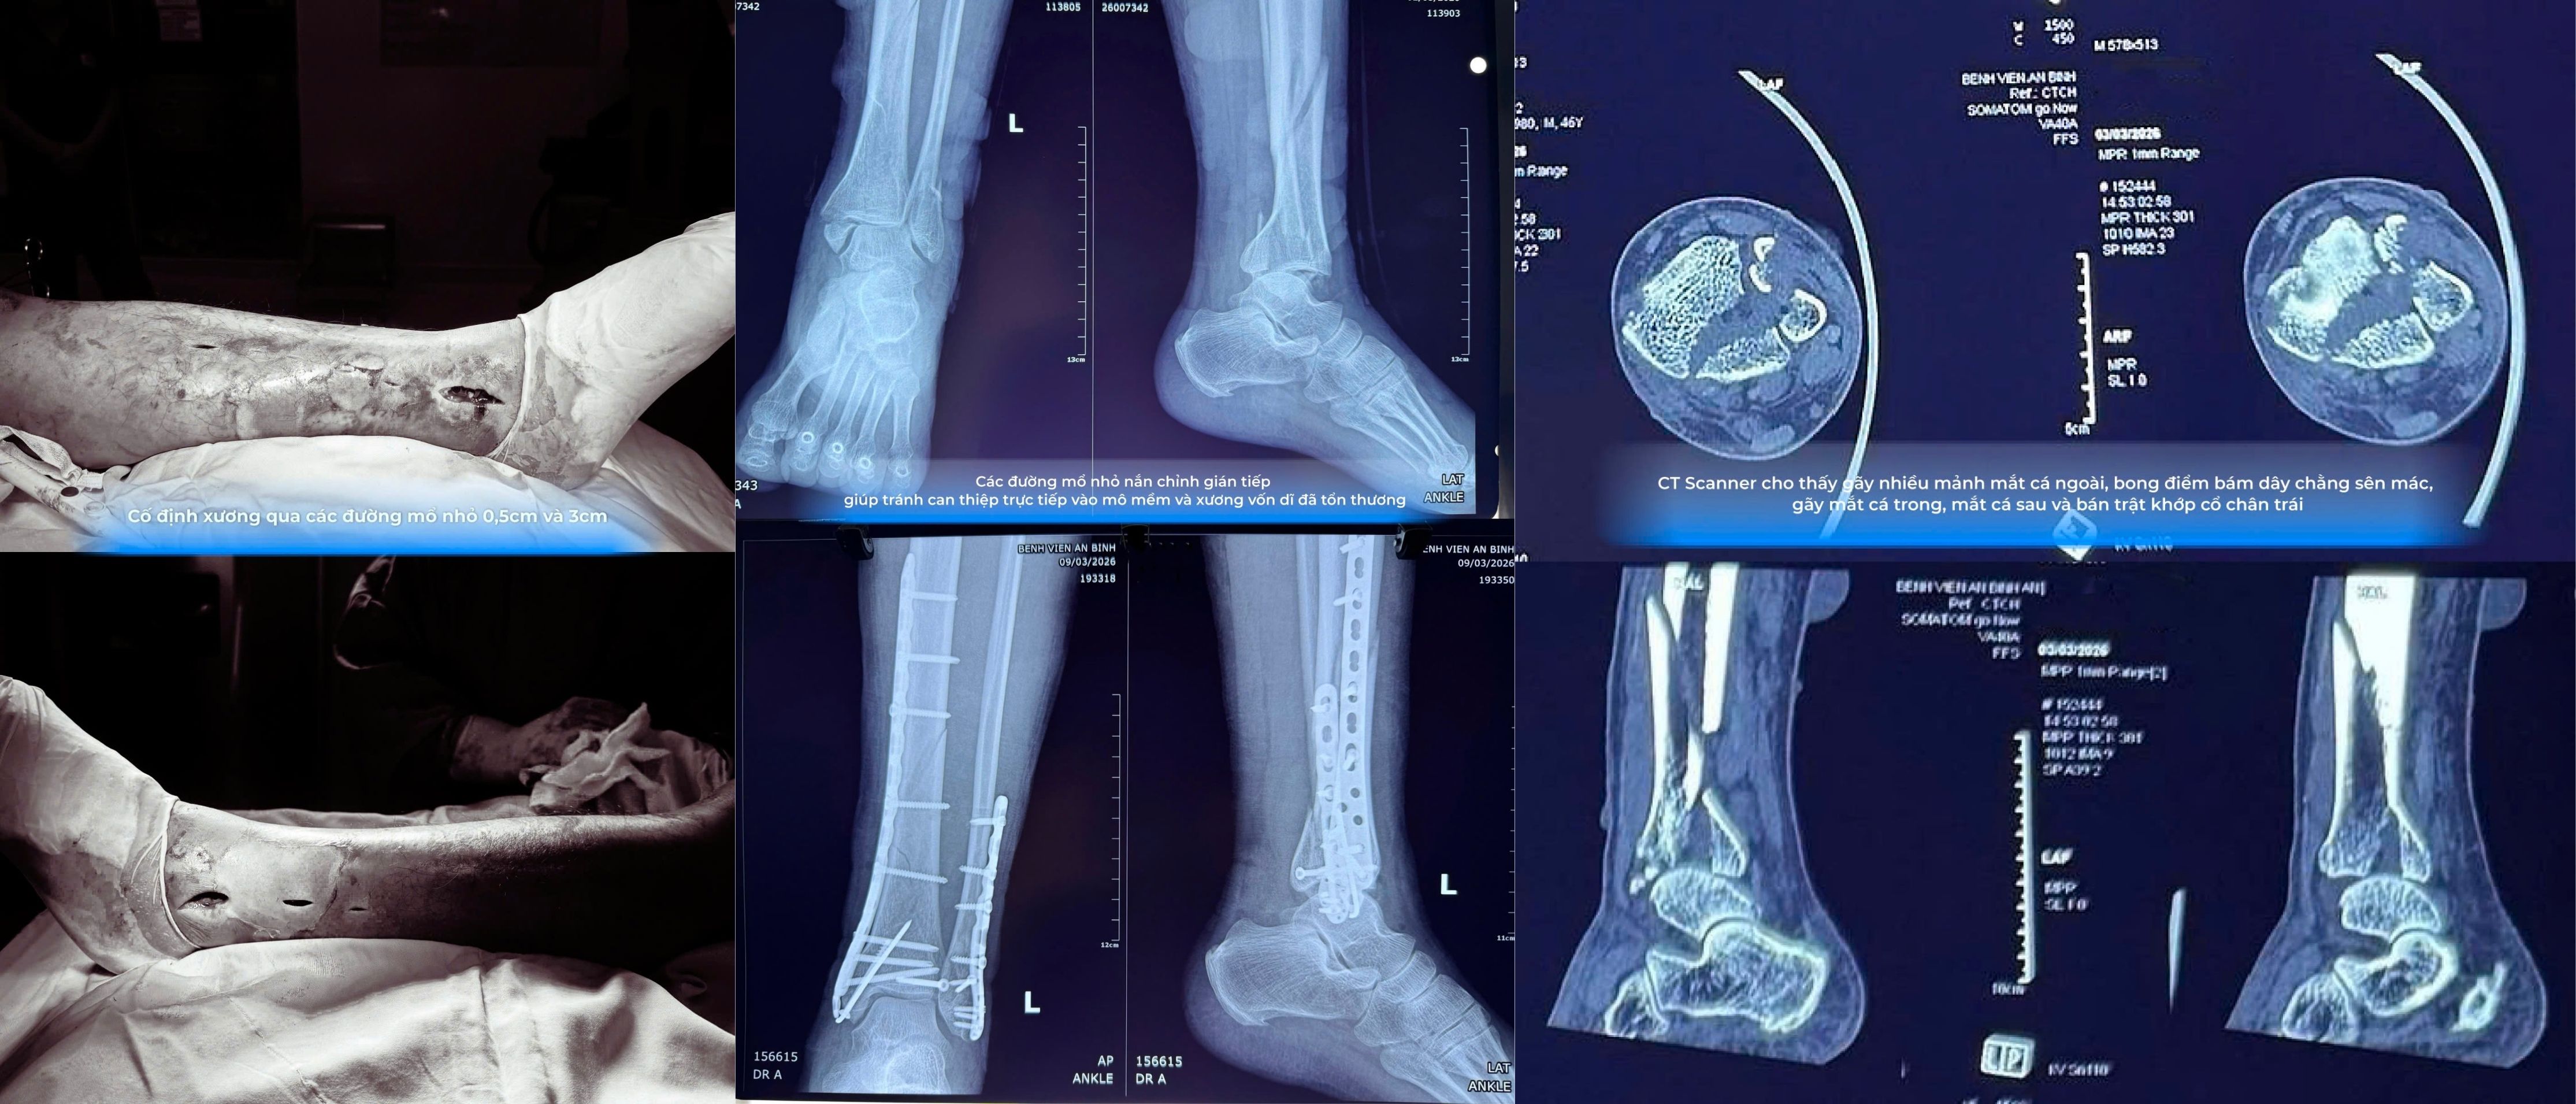

Qua thăm khám lâm sàng và thực hiện các phương tiện chẩn đoán hình ảnh như X-quang và CT scanner, các bác sĩ xác định bệnh nhân bị gãy phức tạp 3 mắt cá chân, gãy 1/3 dưới xương chày, bán trật khớp cổ chân, kèm rối loạn dinh dưỡng mô mềm và viêm mô bào cẳng bàn chân trái do đắp thuốc.

Để đảm bảo an toàn cho người bệnh, các bác sĩ áp dụng chiến lược điều trị hai giai đoạn. Trước tiên là kiểm soát nhiễm trùng và ổn định mô mềm, ưu tiên xử lý tình trạng viêm mô bào và nuôi dưỡng lại vùng da tổn thương. Sau khi mô mềm ổn định, ê-kíp mới tiến hành phẫu thuật can thiệp vào xương.

Ở giai đoạn phẫu thuật, các bác sĩ áp dụng kỹ thuật kết hợp xương xâm lấn tối thiểu với các đường mổ nhỏ thay vì phương pháp bóc tách rộng như trước đây. Kỹ thuật này cho phép nắn chỉnh ổ gãy chính xác dưới sự hỗ trợ của hệ thống X-quang trong mổ theo thời gian thực, đồng thời hạn chế tác động trực tiếp vào vùng xương và mô mềm vốn đã tổn thương.